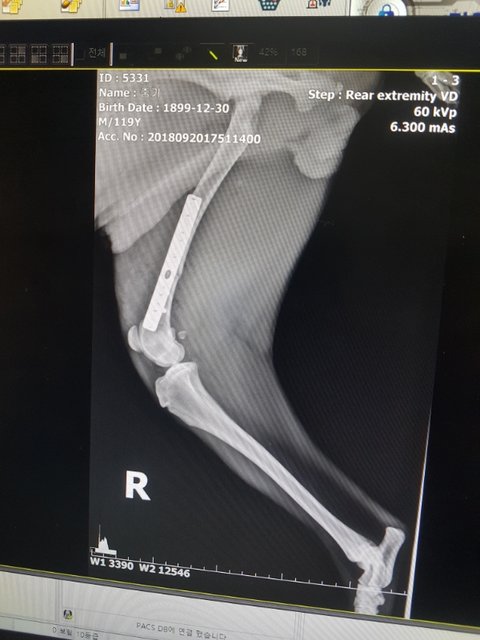

수술도 아주 잘되었다고 합니다.